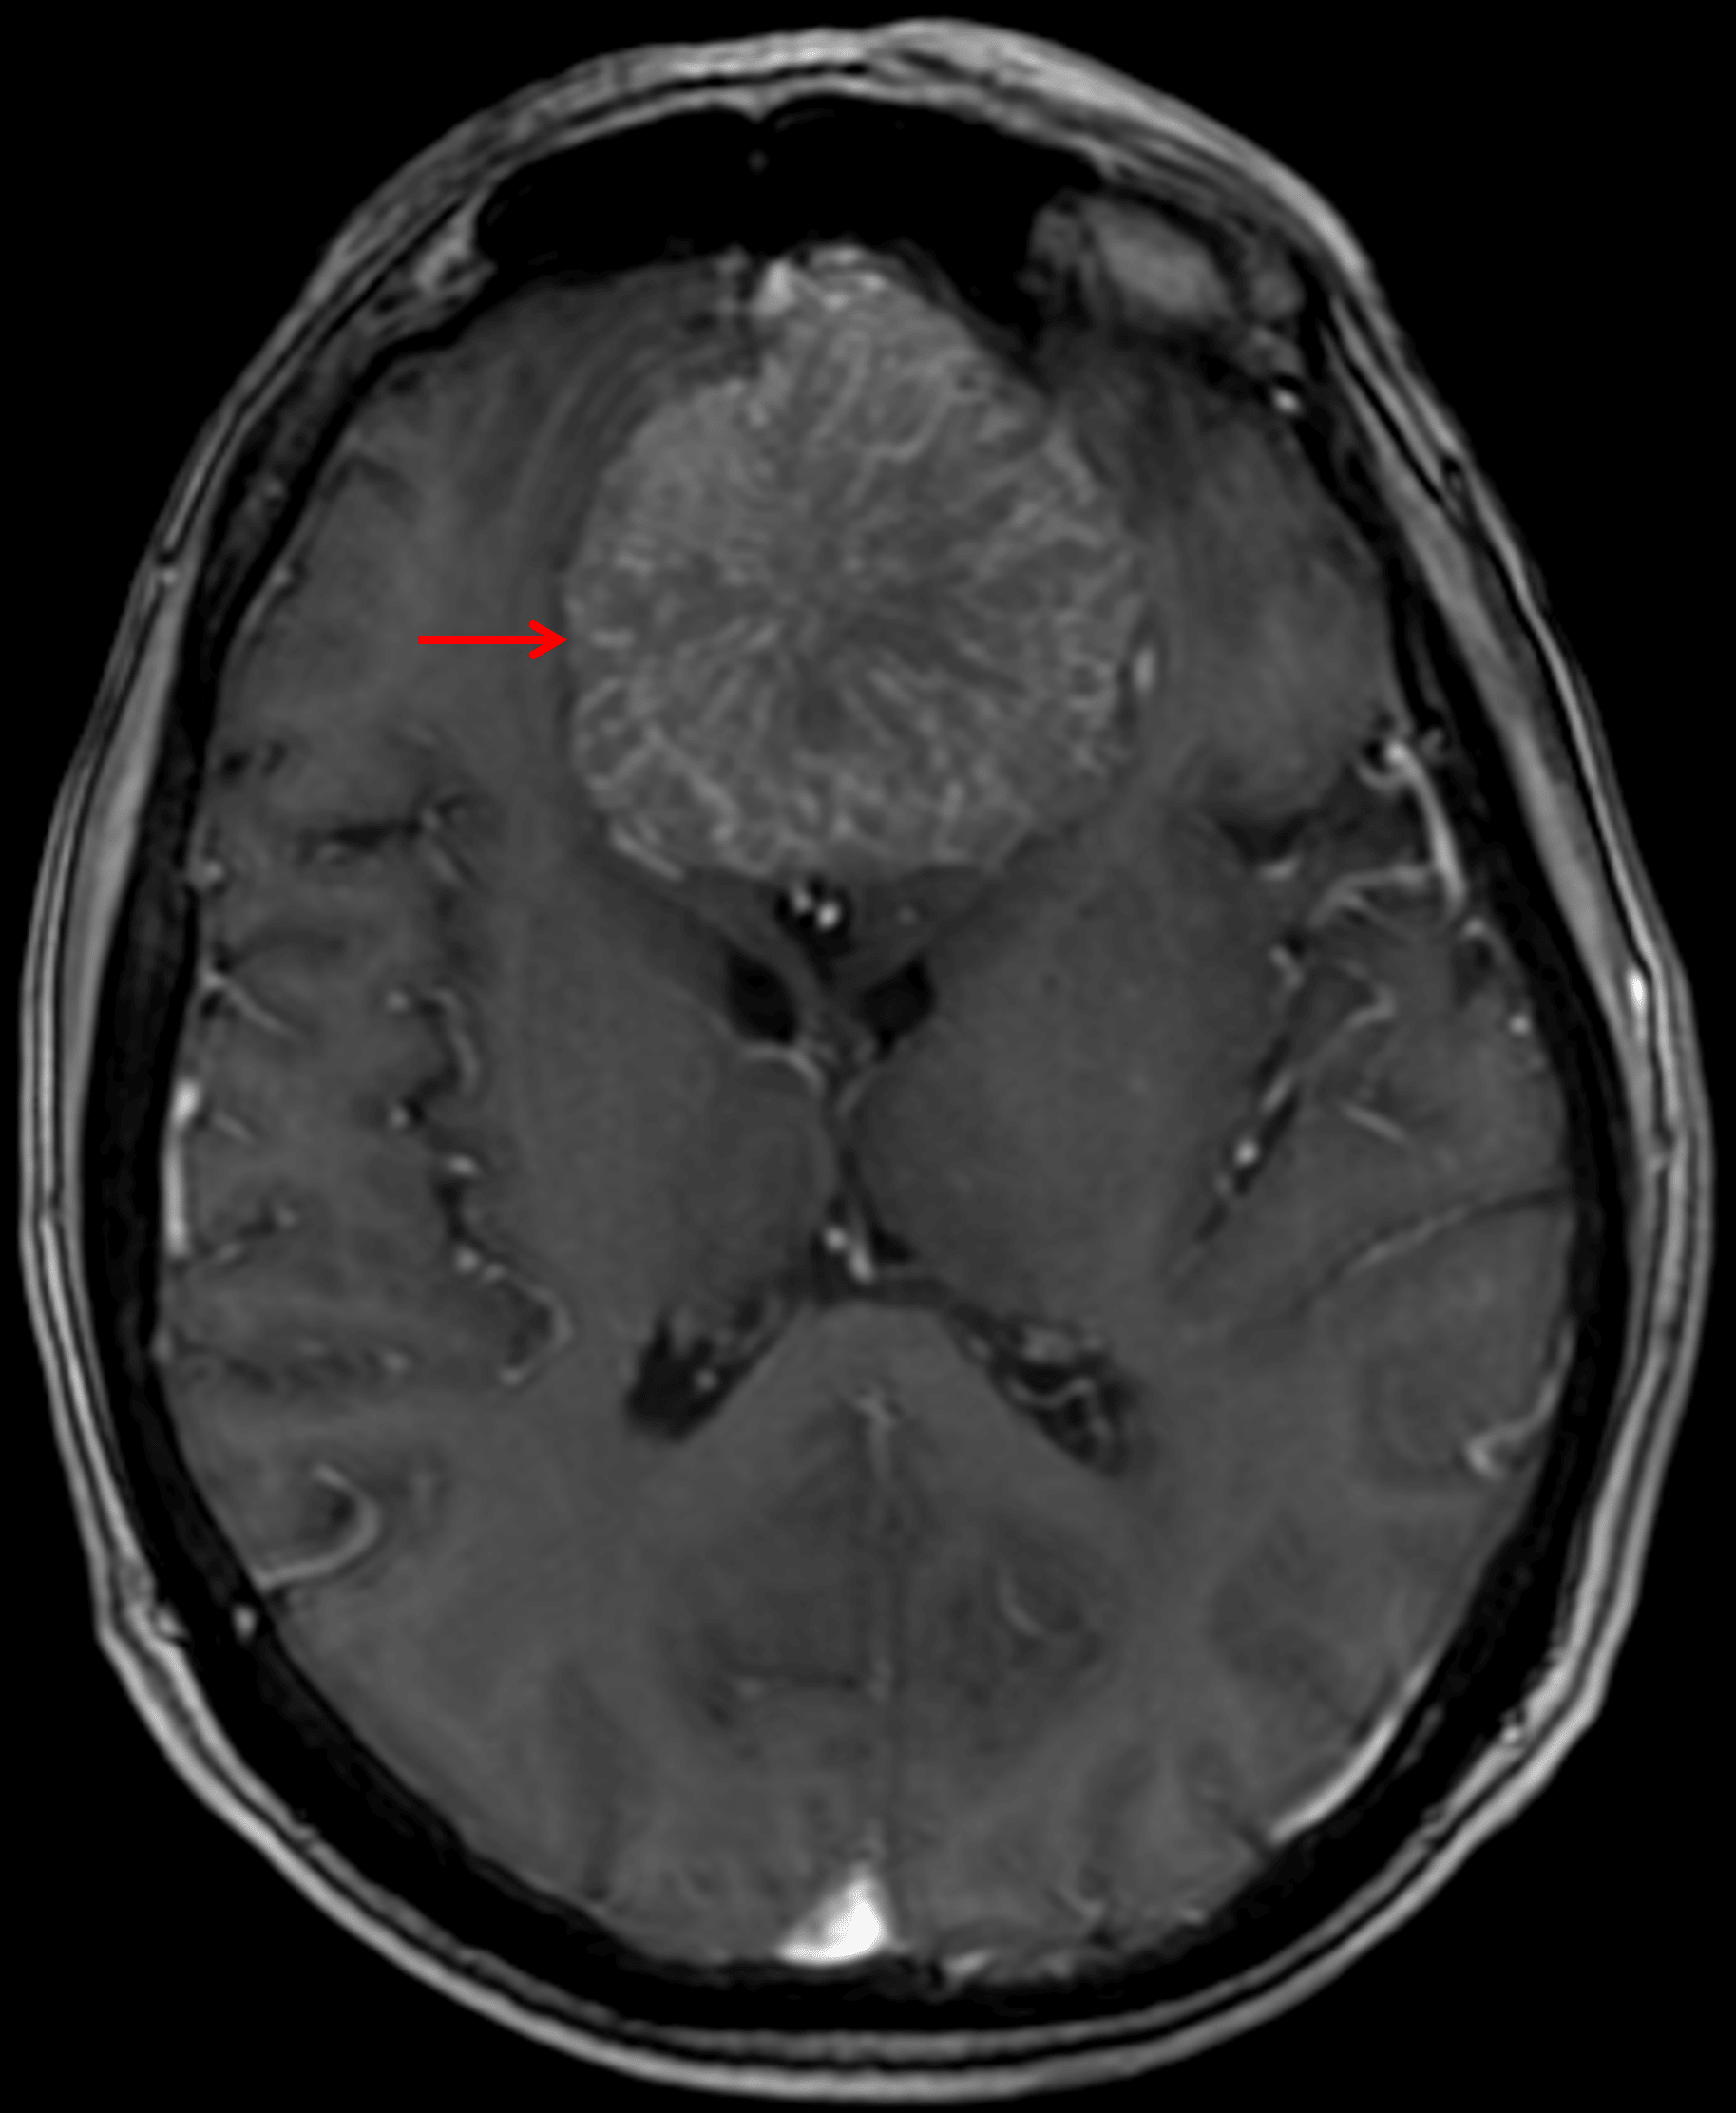

- Diffuse enhancement with radiating internal vascularity

Internal spoke-wheel vascularity on postcontrast imaging (red arrow).